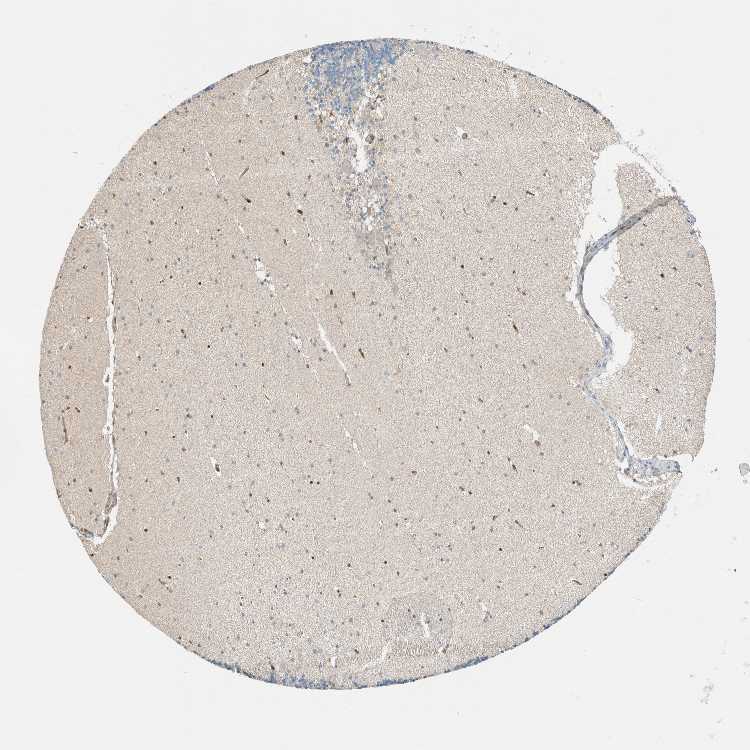

CEREBELLUM - Antibody stainingi

Antibody staining in the annotated cell types in the current human tissue is reported as not detected, low, medium, or high, based on conventional immunohistochemistry profiling in selected tissues. This score is based on the combination of the staining intensity and fraction of stained cells.

Each image is clickable and will lead to virtual microscopy that enables deeper exploration of all samples and also displays staining intensity scores, fraction scores and subcellular localization as well as patient and tissue information for each sample.

Antibody HPA023566

Purkinje cells Not detected

Cells in granular layer Not detected

Cells in molecular layer Not detected